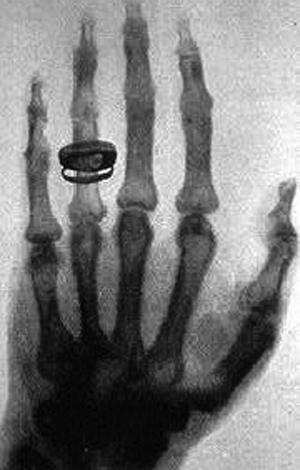

Рентген [26]

Иллюстрация к книге — Ликвидаторы. Чернобыльская комедия [_05.jpg]

Год 1895. Вюрцбург, Германия.

Лаборатория Физического института местного университета. Поздний вечер.

Профессор Конрад Рентген заканчивает свой рабочий день – тушит освещение, делает шаг к двери, снимает с вешалки шляпу…

…и замирает! Где-то в темноте, за черными контурами устройств, – загадочное зеленоватое мерцание!

Удивленный, Конрад Рентген осторожно идет в темноте на этот слабый источник света.

Зеленовато мерцает… кусок картона!

Он, впрочем, не совсем обычный: накануне его покрыли флуоресцентным химическим составом – платиноцианатом бария.

Но почему он сейчас светится?! Флюоресценция – мерцание, которое Рентген сейчас видит перед собой, – возникает только тогда, когда на соответствующее вещество попадают какие-то лучи. А какие могут быть лучи в полном мраке совершенно темной лаборатории?!

Кусок картона, словно издеваясь, разливает вокруг себя слабое загадочное сияние… На светящейся поверхности – темная линия тени, похожая на лукавую ухмылку…

Рентген внимательно оглядывается. С чего бы это флуоресцентному составу светиться?

– Забыл отключить!

Источник высокого напряжения! От него провода идут к газоразрядной трубке Крукса… Но ведь она надежно прикрыта толстым черным картоном, который не пропускает – не может пропускать в принципе! – видимый свет…

Рентген отключает трубку Крукса – сияние платиноцианата бария тут же исчезает.

Включает – зеленоватая флуоресценция картона появляется вновь…